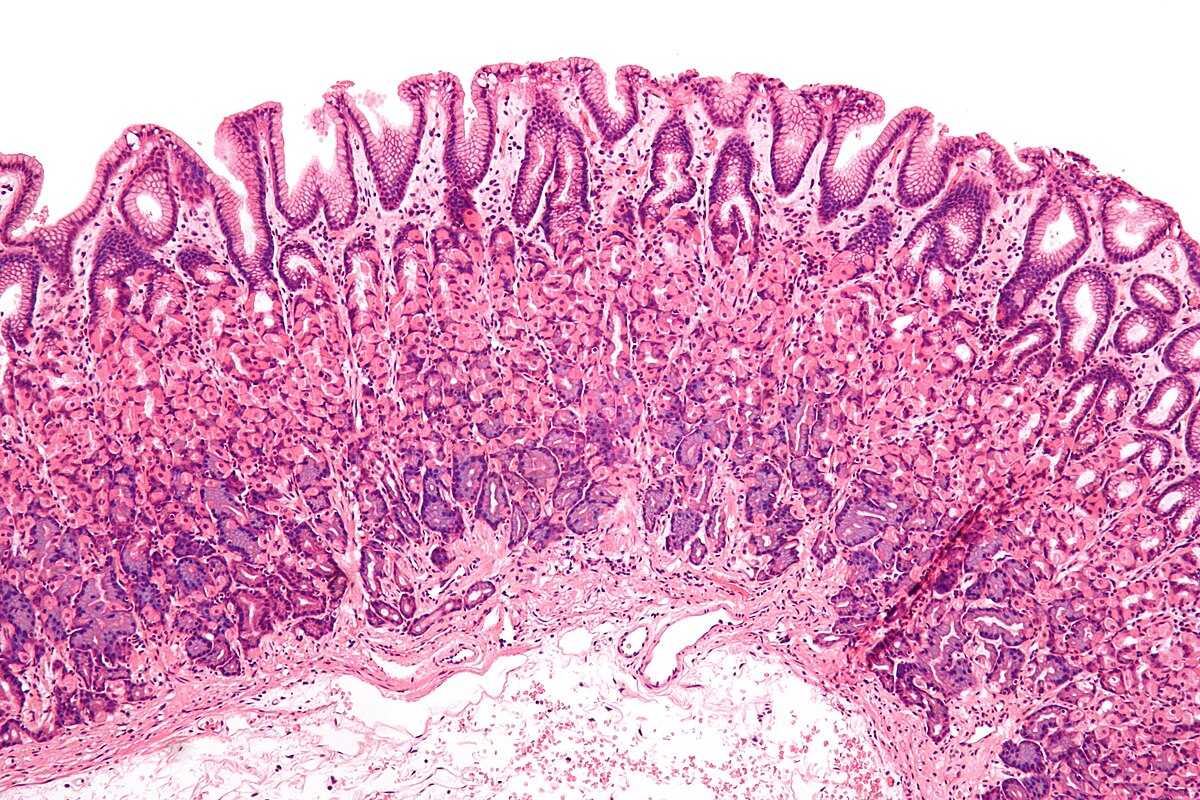

Общий план строения пищеварительной трубки. Особенности слизистой оболочки, ее эпителия в пищеводе и разных отделах желудка. Железы пищевода. Железы желудка разных отделов. Место переходов: из пищевода в желудок и из желудка в кишку.

- Особенности строения слизистой оболочки тонкой кишки: ворсинки, крипты, эпителий, его клеточный состав. Различия в строении двенадцатиперстной, тощей, подвздошной кишки. Морфологическая характеристика толстой кишки, клеточный состав эпителия крипт. Лимфоидная ткань тонкой и толстой кишки.